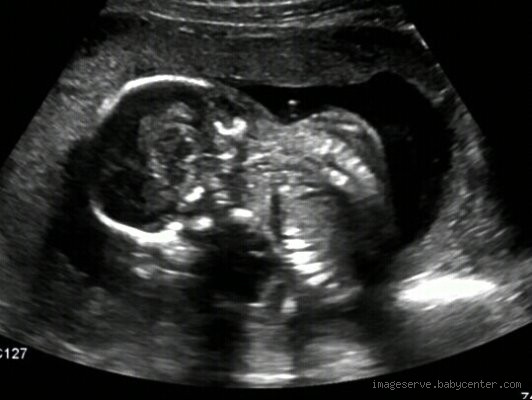

Honestly, the first trimester screening is one of the most common methods to assess the risk of Down syndrome. This screening involves a blood test along with an ultrasound, known as the nuchal translucency screening. The blood test looks at two proteins in your blood, and the ultrasound measures the fluid at the back of your baby’s neck. If there’s an excess amount, it could suggest a higher risk of Down syndrome.

Honestly, ultrasounds can give some clues, but they’re not foolproof. A detailed ultrasound can sometimes pick up physical markers that might indicate a higher risk of Down syndrome, such as certain facial features or abnormalities in the baby’s heart. However, these indicators alone are not enough to diagnose the condition.